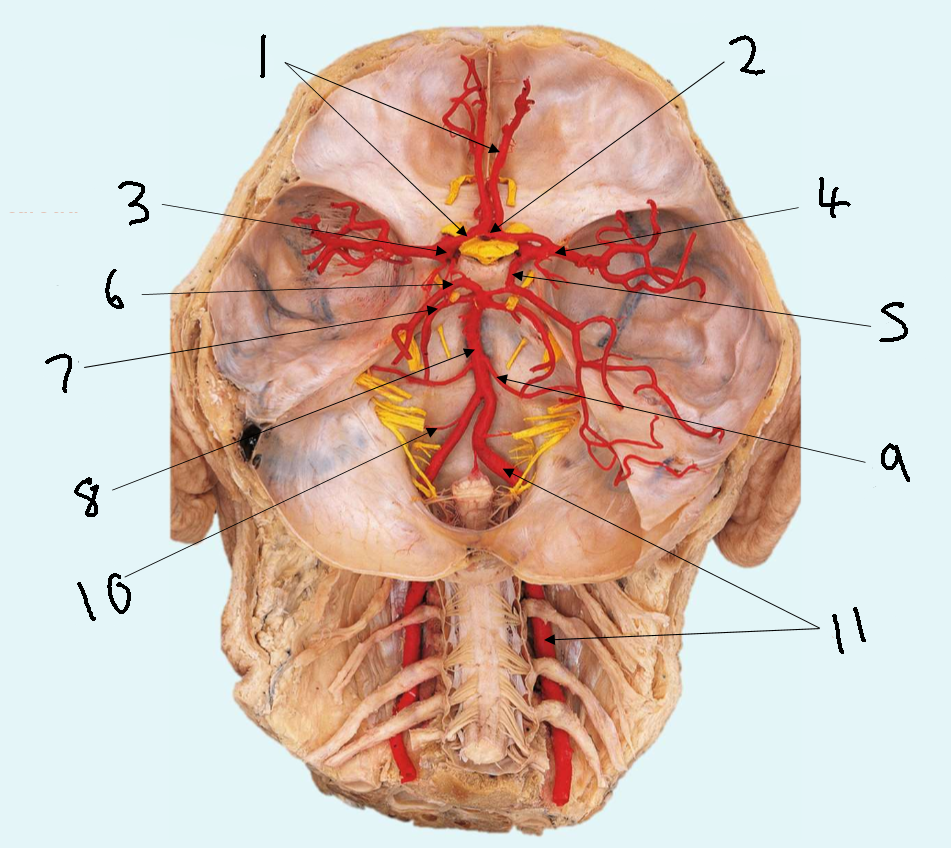

What is 1?

anterior communicating artery

What is 2?

anterior cerebral artery

What is 3?

middle cerebral artery

What is 4?

internal carotid artery

What is 5?

posterior communicating artery

What is 6?

posterior cerebral artery

What is 7?

superior cerebellar artery

What is 8?

pontine arteries

What is 9?

basilar artery

What is 10?

anterior inferior cerebellar artery

What is 11?

vertebral artery

What is 12?

posterior inferior cerebellar artery